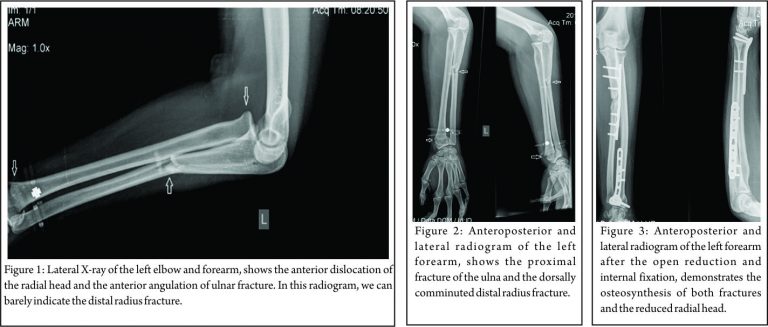

A 25-year-old woman was admitted to our emergency department after a fall from a chair onto her outstretched left hand. Due to mild alcohol consumption, communication with her was unsatisfactory. She complained of pain and inability to use her elbow, while no other injuries were found. She had a clear medical history, with no comorbidities, except smoking. Physical examination revealed swelling and “dinner fork” deformity of her left wrist, tenderness over her left elbow without any bruises or open wounds, while no obvious neurovascular injury was recognised. Frontal and lateral plain roentgenograms of her left forearm revealed a type-1 Bado Monteggia lesion accompanied with an ipsilateral type 1 Frykman distal radius fracture (Colles’ fracture) with dorsal comminution (Fig. 1, 2).

Fortunately, no other fractures were found around her elbow, such as coronoid process or radial head fracture. Presence of such associated injuries compromises the final outcome. The patient was operated on within 8 h after admission, under general anesthesia and tourniquet. At the operating room, the neurological examination was repeated, but no neurological disorder was indicated. The ulna was anatomically reduced and fixed through the classical lateral approach between flexor and extensor carpi ulnaris. Osteosynthesis was performed using a dynamic compression plate (3.5 mm limited contact dynamic compression plate [LC-DCP]). Intraoperative, fluoroscopy showed a spontaneous reduction of the anteriorly dislocated radial head after the ulna’s fixation. Subsequently, through a Henry approach, the distal radius fracture was reduced and fixed with a 3.5 mm T-shaped buttress locking plate (Fig. 3).

Intraoperatively, after the fixation of both fractures, the elbow was found to be stable in all directions with a full range of motion of wrist, elbow, and forearm. The post-operative course was uneventful, and our patient was discharged 2 days after surgery with a dorsal plaster splint. The cast was removed 2 weeks after surgery, and then gradually the mobilization began. The range of wrist (arc: 108°) (Fig. 4) and elbow (arc: 0–135°) (Fig. 5) motion, as well as the supination and pronation (overall arc: 175°) of the forearm recovered completely 2.5 months postoperatively (Fig. 6).

Roentgenograms and clinical evaluation showed completed bone union of both fractures’ sides 3.5 months after surgery (Fig. 7, 8). The patient returned to her daily routine within 4 months following injury. At last follow-up, 6 months postoperatively, the Broberg and Morrey (98/100) and Quick Dash scores (2.27% of disability) were excellent, without any decline in motion, strength, and stability, accompanied by no pain.